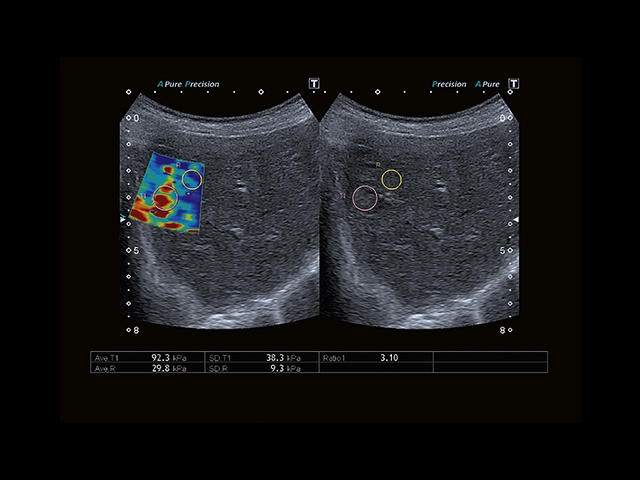

Обновленная версия легендарного УЗ-сканера. Стационарный аппарат экспертного класса Aplio 500 Toshiba NEW, визуализирует анатомические структуры в высоком разрешении. Модель позволяет выявить микрокальцификаты, новообразования, нарушения в работе сердца, сосудов и мышц. Присутствует функция виртуальной эндоскопии, 4D-сканирования, эластометрии тканей, УЗИ с контрастированием. За повышение качества изображения отвечают технологии ApliPure и Superb Microvascular Imaging. Первая задействует возможности пространственного и частотного кодирования, формирует цельный визуальный ряд с сохранением клинических маркеров. Вторая улучшает отображение микрососудистого русла, используя доплеровский эффект. Модель оснащена 21-дюймовым монитором, имеет 4 активных порта. Возможно подключение педиатрических, интраоперационных, лапароскопических и чреспищеводных датчиков.

Эластография:

Компрессионная

Эластография сдвиговой волной/Эластометрия:

Нет

Компрессионная эластография:

Да